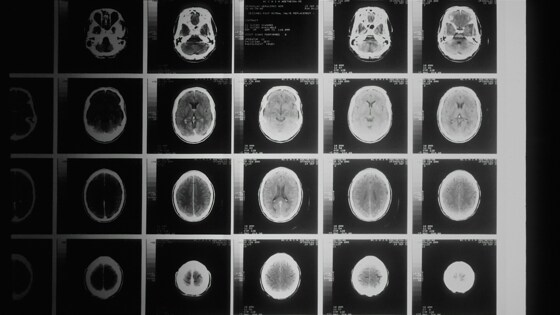

Ученые совершили прорыв в удалении опухолей мозга

Опухоли, которые возникают в головном мозге, являются одними из самых сложных для удаления в нейрохирургии. Ученые предложили новый подход, который позволит снизить риск нежелательных повреждений и послеоперационных осложнений, передает издание Medical Xpress.